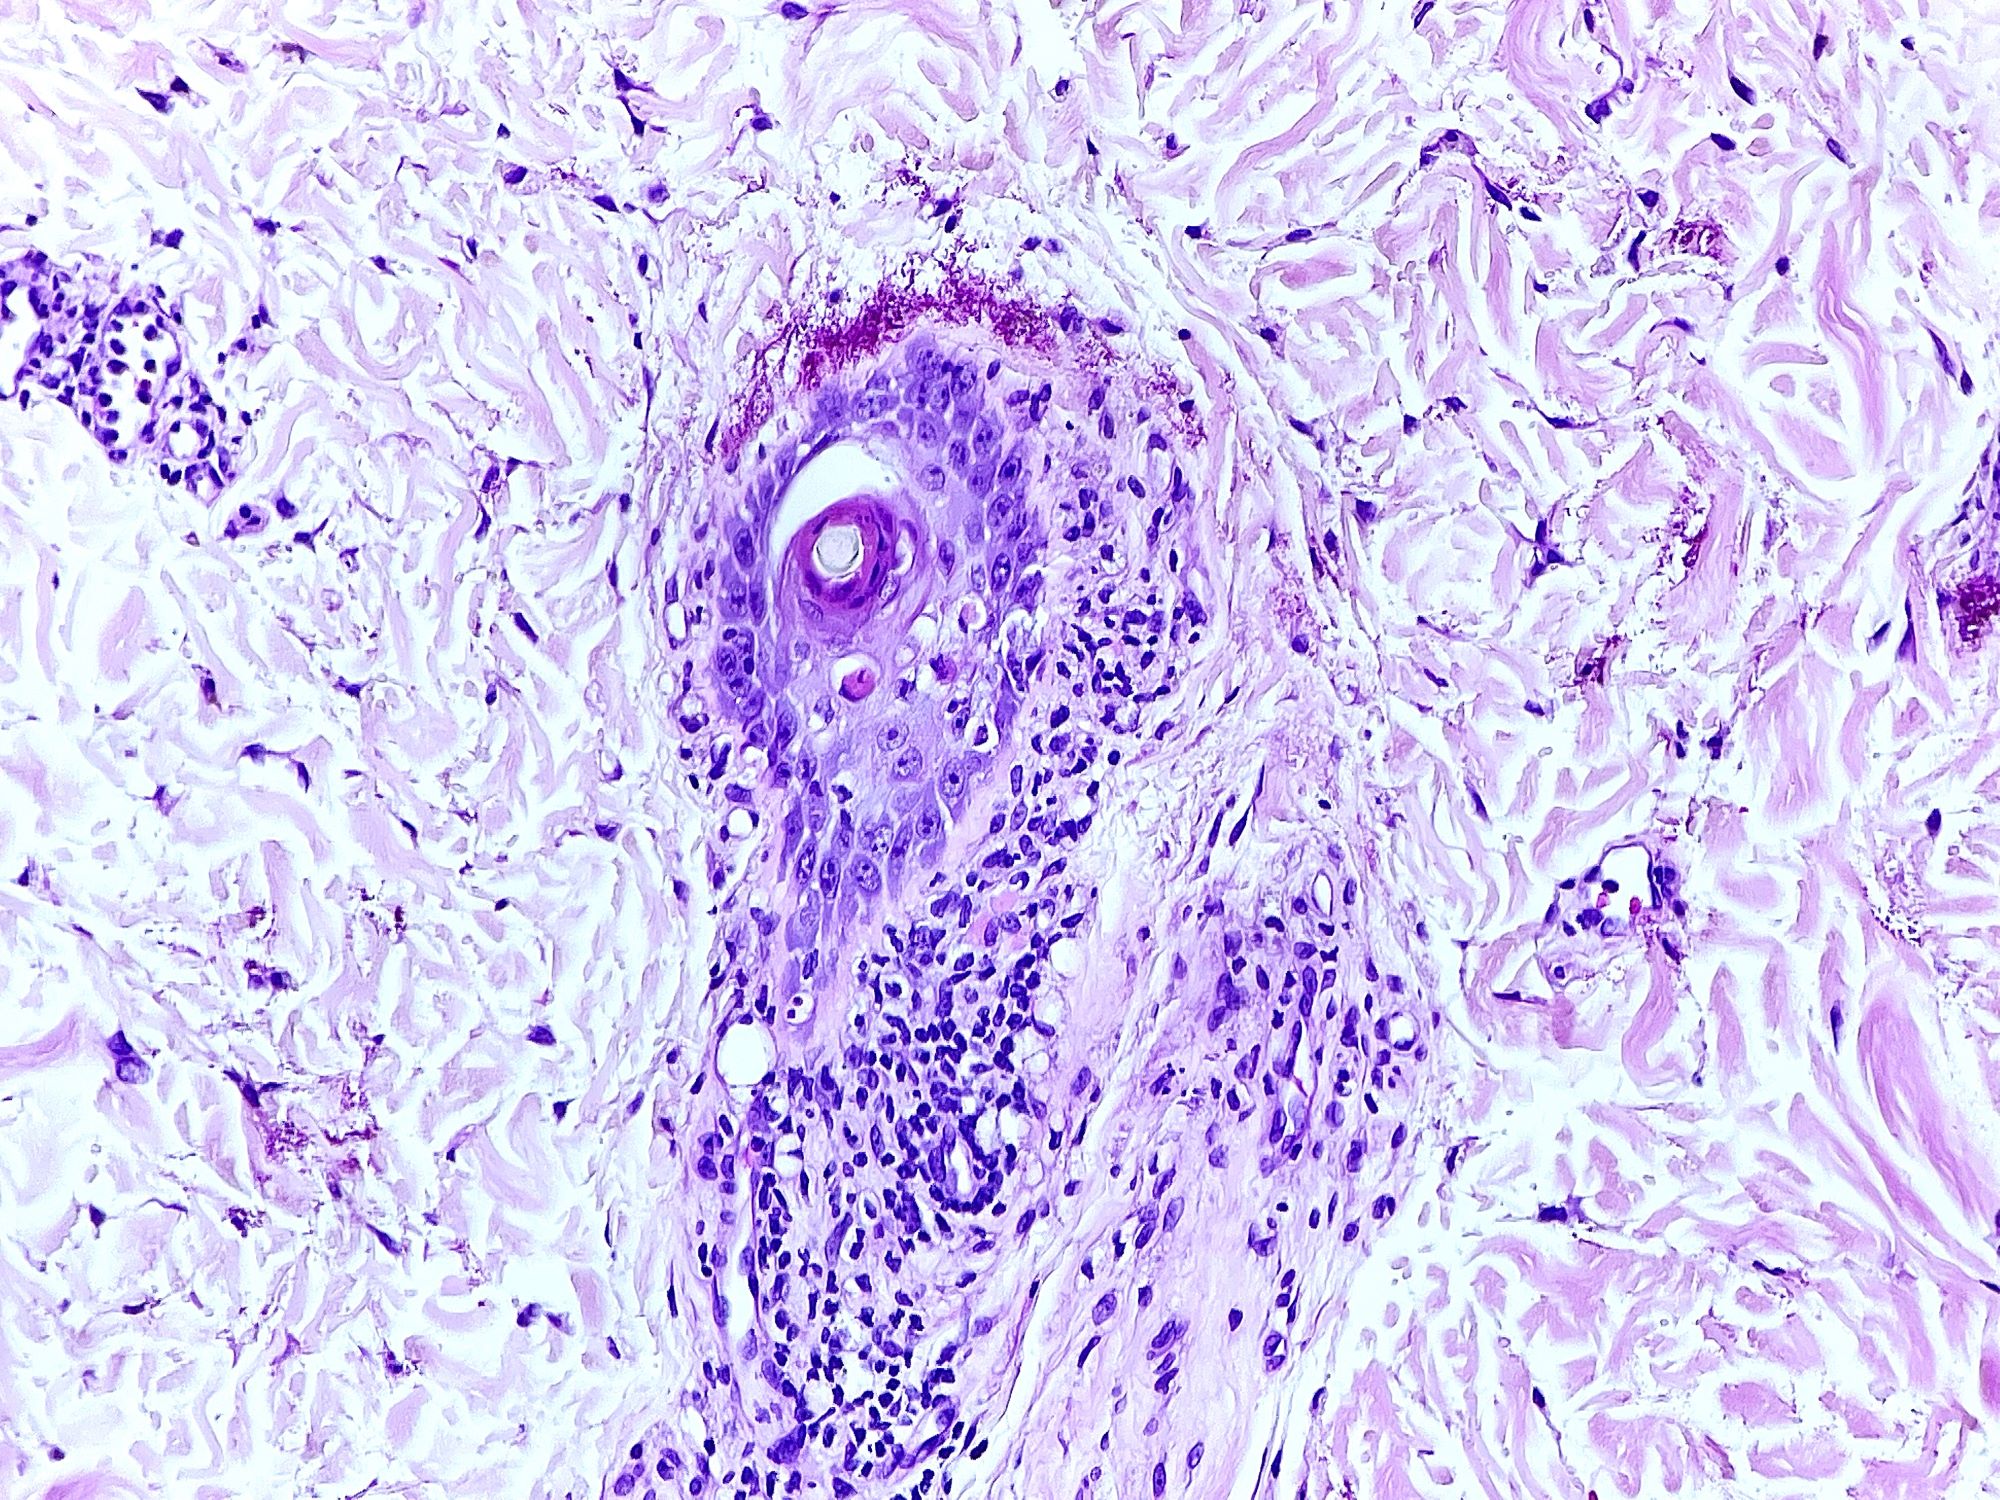

- Chronic GVHD (Biol Blood Marrow Transplant 2015;21:589, Patterson: Weedon's Skin Pathology, 4th Edition, 2015)

- Chronic lichenoid GVHD

- Acanthosis, orthohyperkeratosis, parakeratosis with hypergranulosis

- Underlying band-like lymphocytic infiltrate with basal layer vacuolization and apoptotic keratinocytes

- Periadnexal inflammation can be present

- May be difficult to distinguish from lichen planus without clinicopathologic correlation; satellite cell necrosis is the most helpful clue in GVHD biopsies to distinguish it from lichen planus

- Chronic lichenoid GVHD

Microscopic (histologic) images

Contributed by Silvija P. Gottesman, M.D. and Ohoud Aljarbou, M.D.